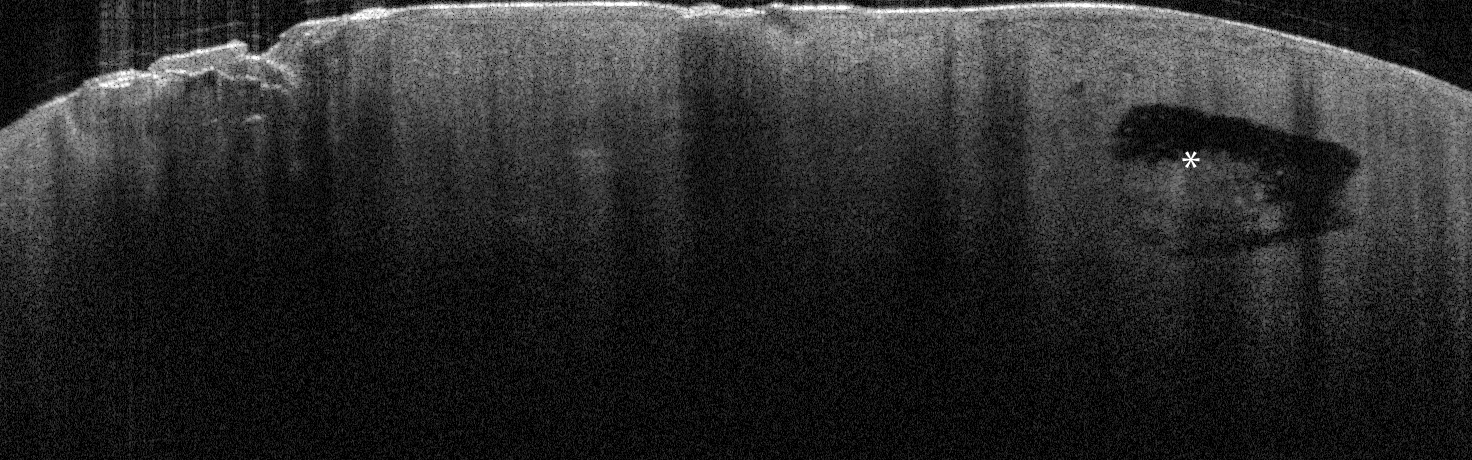

VA33: Superior Nasal Ala, Basal Cell Carcinoma, Nodular

- * indicate areas of necrotic cells not yet undergone liquifactive necrosis